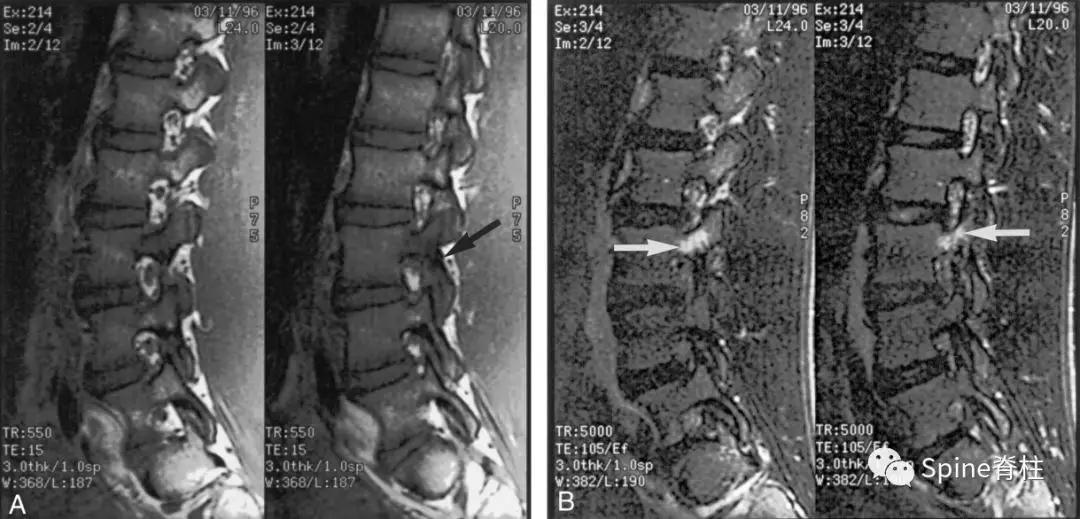

图:孤立的峡部水肿信号,提示L5右侧峡部裂(1级)

16岁的足球运动员诉右腰部疼痛。A:右侧T1加权像可见腰5峡部和椎弓根呈低信号(箭头);B:右侧T2加权像可见腰5峡部、椎弓根和关节突呈高信号(箭头)。

图:T2水肿信号且峡部皮质不连续断裂

提示L3左侧峡部裂(2级)

17岁的篮球运动员诉腰痛。A:T1像,左侧腰3峡部呈不连续的低信号(箭头);B:T2像,左侧腰3椎弓根和峡部呈高信号(箭头)

图:峡部完全断裂,断端存在明显间隙,且T2像明显水肿信号,提示L5左侧峡部裂(3级)

16岁的足球运动员,诉腰痛,以左侧为重。A:T1像可见腰5左侧峡部完全断裂(箭头);B:T2像,腰5左侧峡部、椎弓根和关节突水肿信号(箭头)

图:峡部完全断裂,但无T2水肿信号

提示为左侧L5峡部裂(4级)

13岁运动员,左侧腰骶部疼痛。A:T1像,左侧腰5峡部完全断裂(箭头);B:T2像,左侧腰5峡部清晰可见,骨质无信号改变,峡部缺损处可见轻微的高信号,提示可能为肉芽组织或积液